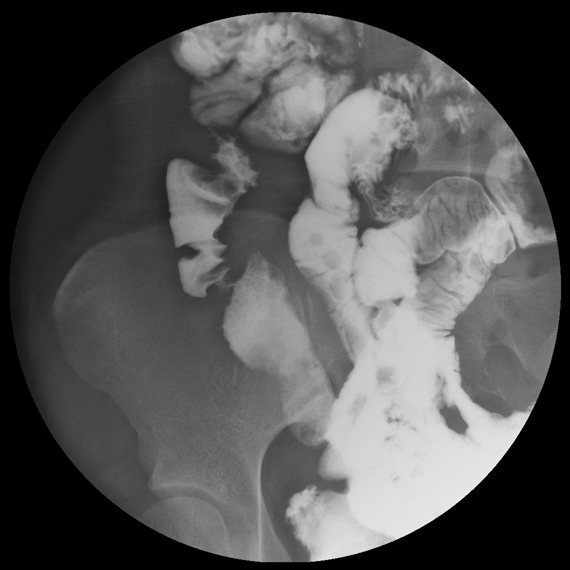

小腸造影検査における回腸の縦走潰瘍および偏側性の壁硬化像

併せて終末回腸に強い狭窄を認める。